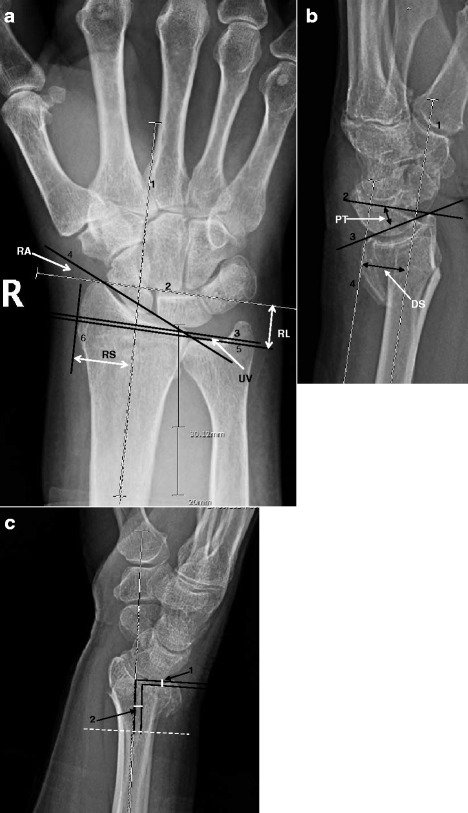

PA and lateral wrist radiographs of a 58-year-old female showing a dorsally displaced distal radius fracture. Key measurements: dorsal tilt 25° (normal 11° volar), radial inclination 12° (normal 22°), radial height 8mm (normal 12mm), positive ulnar variance. Intra-articular step-off of 2mm is visible. This represents an unstable fracture pattern requiring surgical fixation.